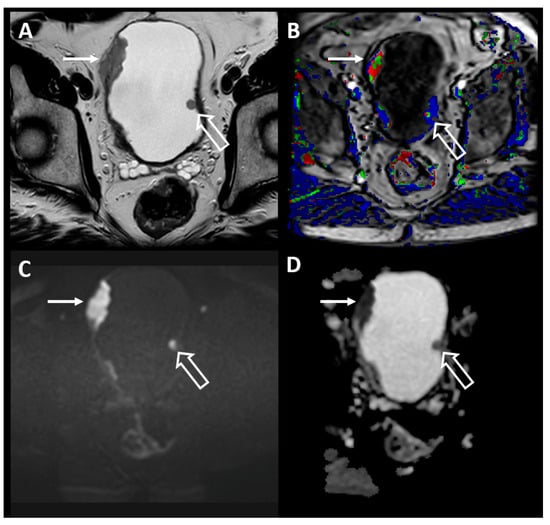

4.4. MRI Findings in Bladder Cancer

4.5. Imaging and Reporting Bladder Cancer with VI-RADS

4.6. TNM Staging of Bladder Cancer with MRI